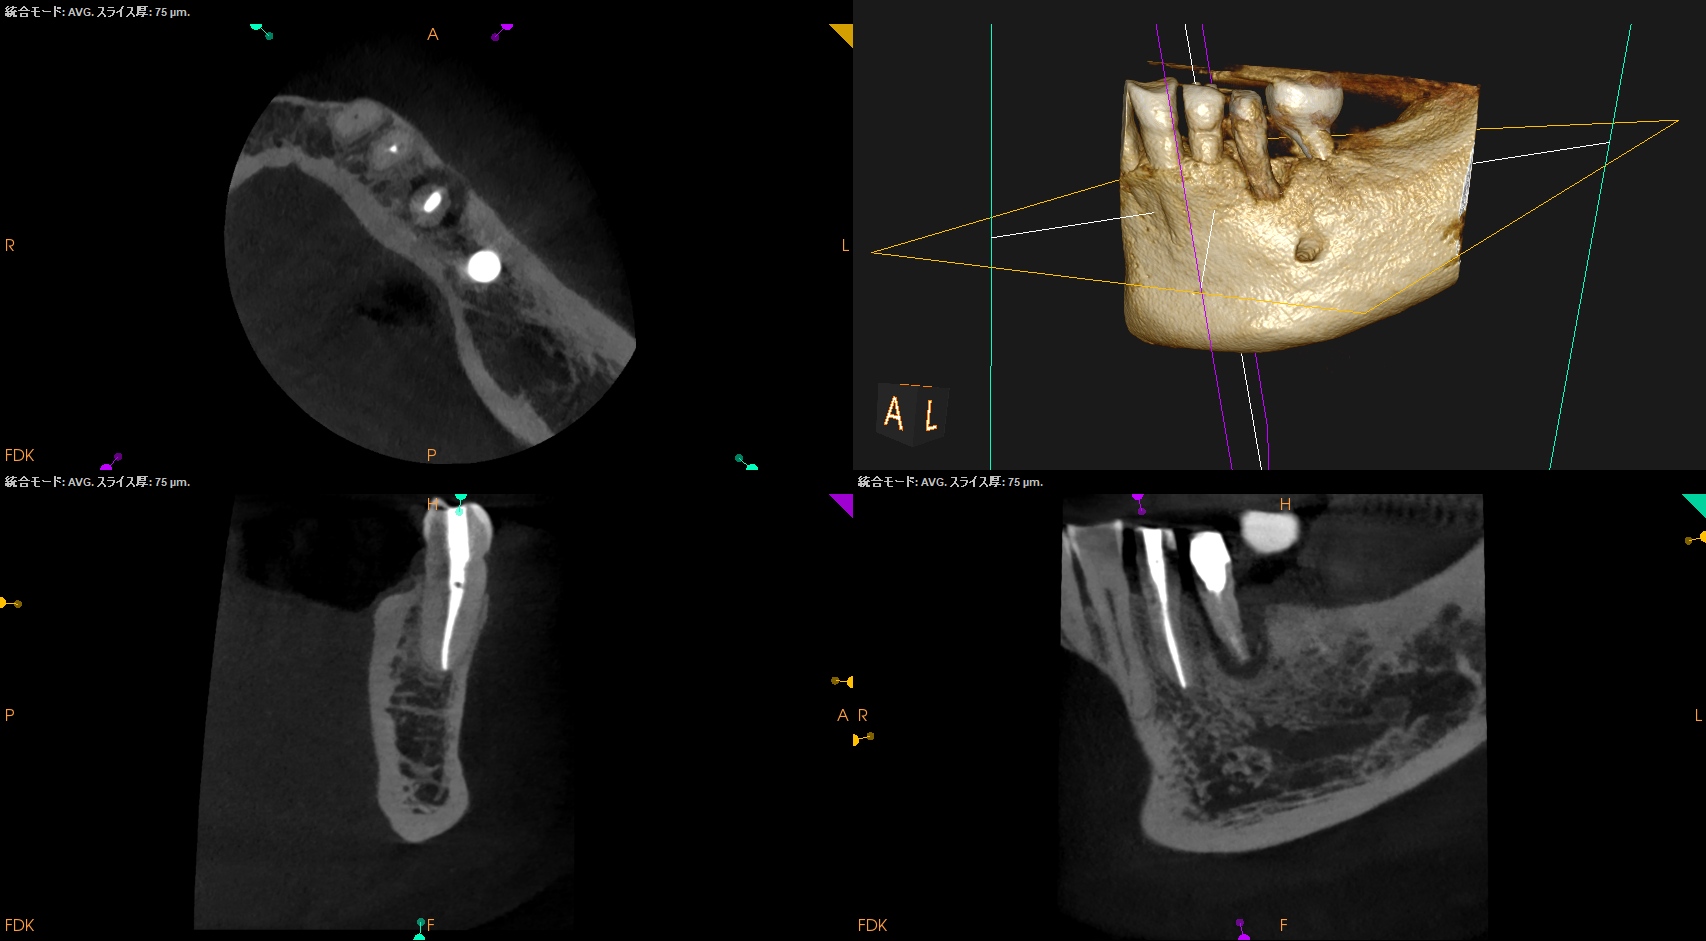

DL部分に直覆的な治療をした痕跡があるので、

歯髄が石灰化している。

穿孔を引き起こさせかねない歯牙だ。

が、術前にCBCTを撮影すればどこに気をつけるべきか?はあらかじめ判断ができる。